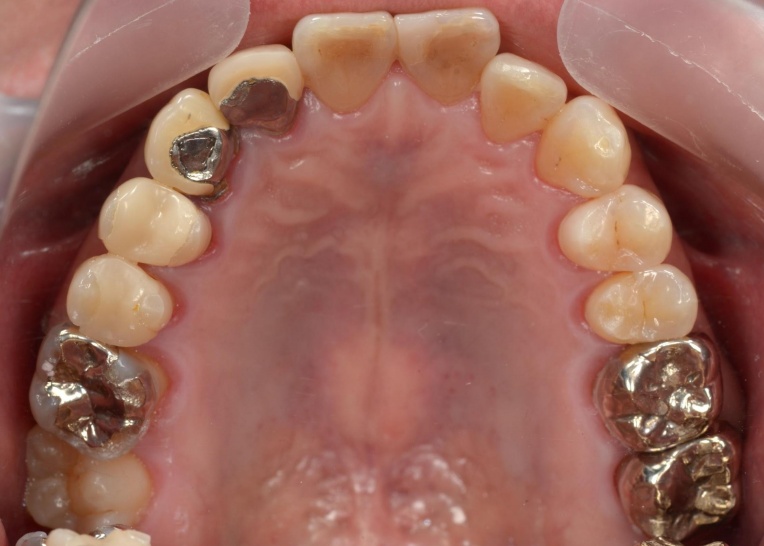

治療前

治療中

拝見したところ、右下奥歯(第2大臼歯)が折れていることが確認できました。

また、患者様は下顎が上顎よりも前に出る「反対咬合(こうごう)」、いわゆる受け口の傾向があることがわかりました。